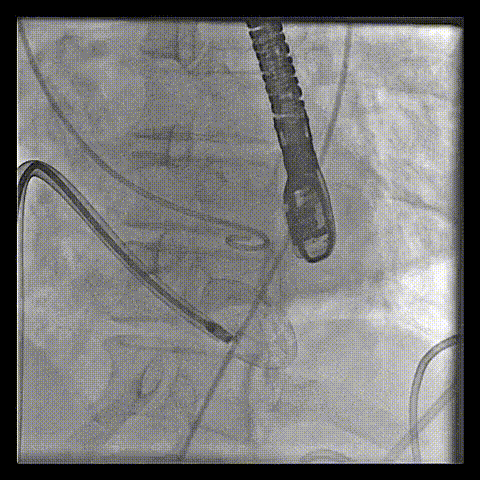

آنژیوپلاستی با رسوب شدید کلسیم در عروقتوسط دکتر عارف فاتحی فوق تخصص آنژیوگرافی و آنژیوپلاستی(قلب